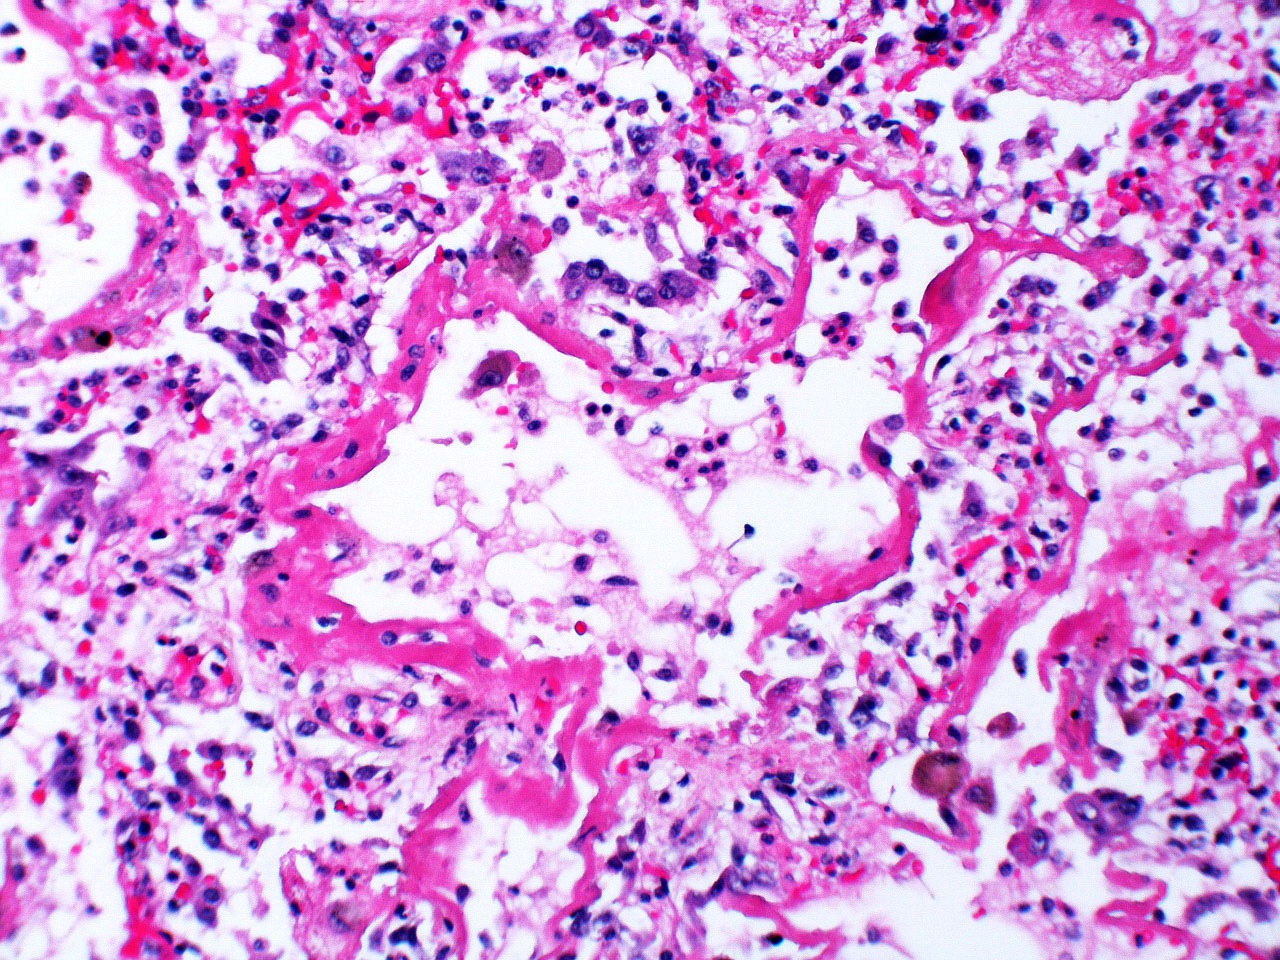

Microscopic (histologic) description

- Histopathology of DAD progresses from exudative (acute) phase through proliferative / organizing (subacute) phase to chronic fibrotic phase roughly corresponding to the period of ARDS (Am J Pathol 1976;85:209, Arch Pathol Lab Med 2010;134:719, Clin Chest Med 2000;21:435, N Engl J Med 2000;342:1334)

- Exudative (acute) phase

- Alveolar change

- Hyaline membranes on alveolar duct or sacs

- Interstitial and intra-alveolar edema

- Collapsed alveoli

- Epithelial change

- Denudation and necrosis of type I pneumocytes

- Vascular change

- Necrosis of endothelial cells

- Neutrophil aggregation

- Microthromboemboli

- Hemorrhage

- Alveolar change

Microscopic (histologic) images

Contributed by Akira Yoshikawa, M.D. and Yale Rosen, M.D.